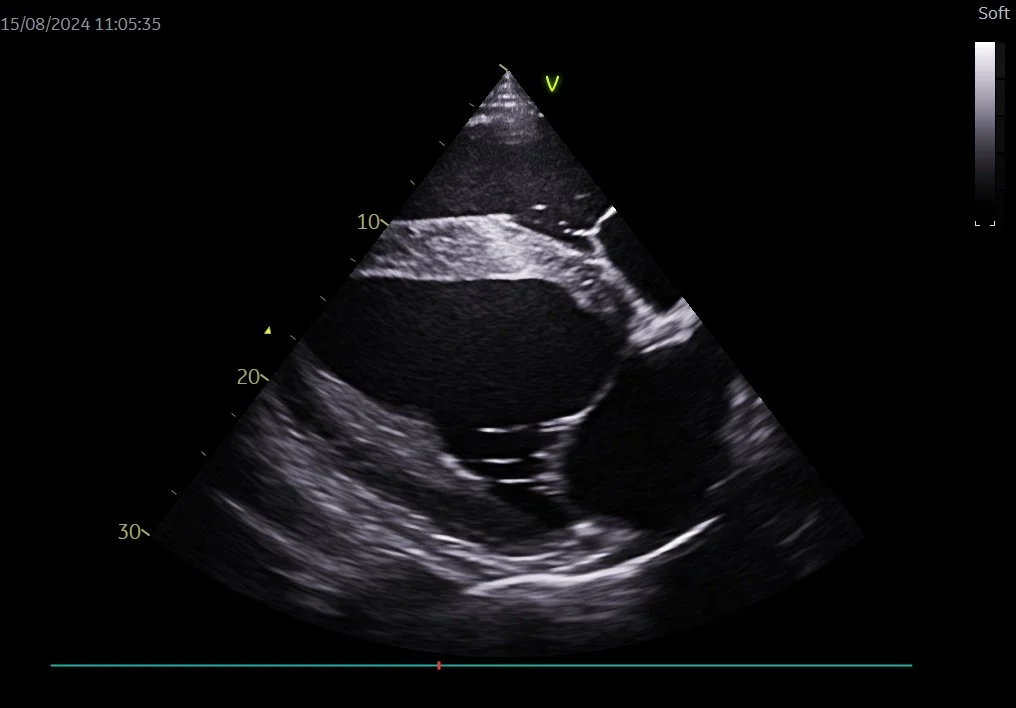

Ultralydsscanning

Ved en ultralydsscanning af hjertet undersøges hjerteklapper, hjertekamre, muskulaturen, hjerteposen, de store blodkar og blodgennemstrømningen i hjertet.

Hjertet scannes i forskellige vinkler, og der optages billeder og videoer. Undersøgelsen varer ca. 1 time, og gøres uden bedøvelse.

Billederne analyseres efterfølgende, og der foretages en række målinger for at kunne vurdere hjertets sundhedstilstand og funktion.